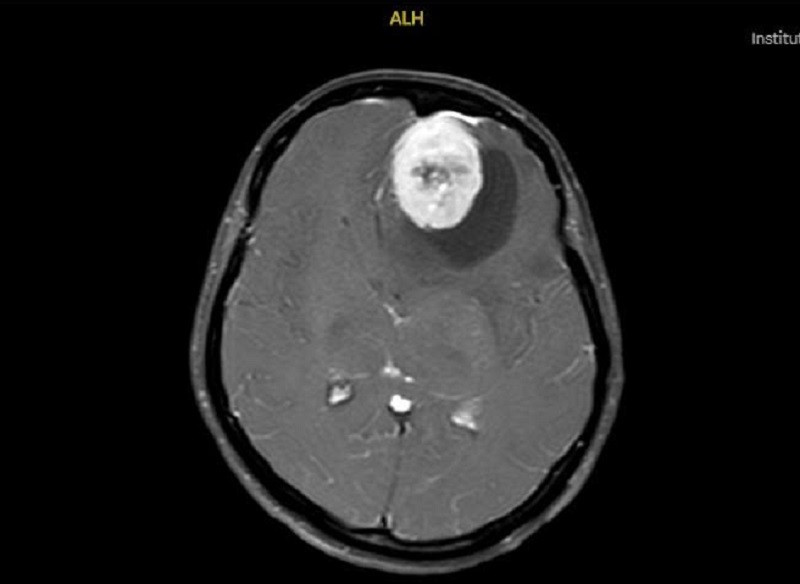

Trên hình ảnh kiểm tra, các bác sĩ ghi nhận khối u khổng lồ

Tại khoa Cấp cứu, sau thăm khám và chỉ định chụp MRI sọ não, các bác sĩ phát hiện một khối u màng não vùng trán có kích thước khoảng 6cm, lớn tương đương một quả trứng gà. Khối u chèn ép mạnh nhu mô não, gây phù não lan rộng và làm lệch đường giữa lên đến 15mm. Đây là mức độ chèn ép rất nặng, có nguy cơ dẫn đến rối loạn ý thức, hôn mê sâu và đe dọa trực tiếp tính mạng nếu không được can thiệp kịp thời.